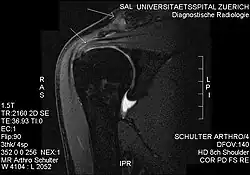

Обычные рентгеновские снимки плеча могут использоваться для выявления некоторых патологий суставов и изменений в костях, включая акромиально-ключичный артрит, изменения акромиона и кальциноза. Однако рентген не позволяет визуализировать мягкие ткани и поэтому имеет низкую диагностическую ценность[2]. Ультрасонография, артрография и МРТ могут использоваться для выявления патологии мышц вращательной манжеты. МРТ — лучший визуализирующий тест перед артроскопической операцией[2]. Из-за недостаточного понимания патоэтиологии и отсутствия диагностической точности в процессе оценки многими врачами[18] перед вмешательством рекомендуется несколько мнений.